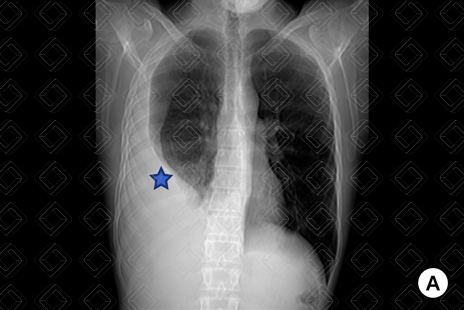

Descrição das figuras 1, 2 e 3: Adolescente de 16 anos, com desconforto respiratório e febre. Imagem A (figura 1): radiografia de tórax evidencia moderado derrame pleural (asterisco). Imagem B (figuras 2 e 3): exame foi complementado com tomografia de tórax com contraste, pela não melhora clínica. Observa-se o derrame pleural (seta vermelha) à direita e os nódulos centrolobulares (seta amarela) com padrão de árvore em brotamento à esquerda, achados muito sugestivos de tuberculose pulmonar, confirmada posteriormente.

• Radiografia de tórax : Em geral, os derrames livres acumulam-se nas porções pendentes dos pulmões. Na radiografia em ortostase, o achado mais precoce é a obliteração do seio costofrênico posterior na imagem em perfil. Volumes maiores passam a ser observados também na incidência frontal. Derrames pleurais volumosos podem ser uma das causas de hemitórax opaco, com aumento das dimensões do hemitórax acometido e desvio das estruturais mediastinais contralateralmente. Lembrando que o uso da radiografia em decúbito lateral com raios horizontais pode ser usado para confirmar o derrame pleural, mas está em desuso devido ao excesso de radiação ionizante (atualmente, nos casos duvidosos, a melhor escolha é a ultrassonografia de tórax). Figura 1;